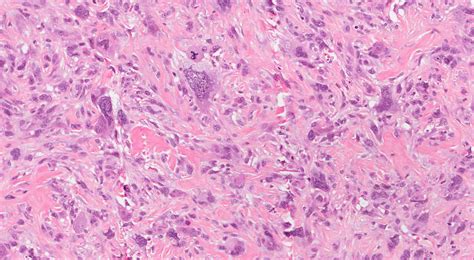

Receiving a medical diagnosis involving the term Spindle Cell Neoplasm can be an overwhelming experience, often filled with uncertainty and concern. To navigate this diagnosis effectively, it is essential to understand what these cells are, how they behave, and why this term is used as a broad descriptor rather than a final, specific diagnosis. At its core, this term refers to a group of tumors characterized by the presence of elongated, spindle-shaped cells when viewed under a microscope. Because many different types of tissue can produce these specific cell shapes, the diagnosis is essentially a starting point for pathologists to determine the exact nature and origin of the growth.

In pathology, the term Spindle Cell Neoplasm is a descriptive classification. It tells a medical team that a biopsy has revealed cells that are longer than they are wide—resembling the shape of a sewing spindle—but it does not immediately clarify whether the tumor is benign (non-cancerous) or malignant (cancerous).

These cells are structural components of the body’s connective tissues, including muscle, fat, fibrous tissue, and nerves. When these cells begin to grow uncontrollably, they form a mass that pathologists identify as having "spindle cell morphology." Because this morphological trait is shared by a vast array of conditions, pathologists must perform secondary testing, such as immunohistochemistry, to identify specific proteins or markers present on the cells.